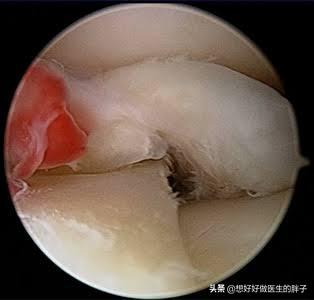

这样破裂的半月板往往会继发出现明显的滑膜炎症,导致患者出现疼痛,下图当中就是由于半月板破裂以后,诱发滑膜炎症的影像学资料,红色的区域就是有明显炎症反应的滑膜。

对于这样的半月板破裂,往往建议进行关节镜手术,根据破裂的具体部位、患者的年龄,以及是否有内科疾病综合情况来决定具体的手术方式。如果能缝合,医生会尽全力给予尝试进行半月板缝合,如果实在不能缝合,那只能尝试进行部分切除或者是全部切除手术。下图就是患者出现明显的半月板层裂,而且有明显的退变,医生还是给与其进行了缝合手术的影像学资料,这样经过缝合的半月板,如果愈合以后,将会对关节造成最小的影响。